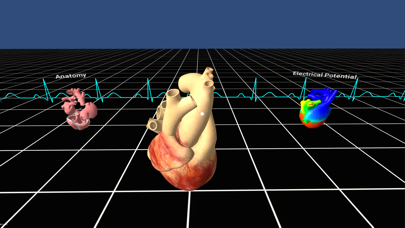

Скриншоты